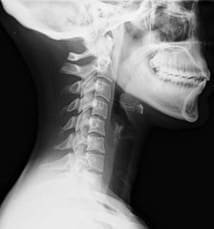

Règle de prédiction clinique pour les cervicalgies whiplash : pertinence par rapport à un examen classique